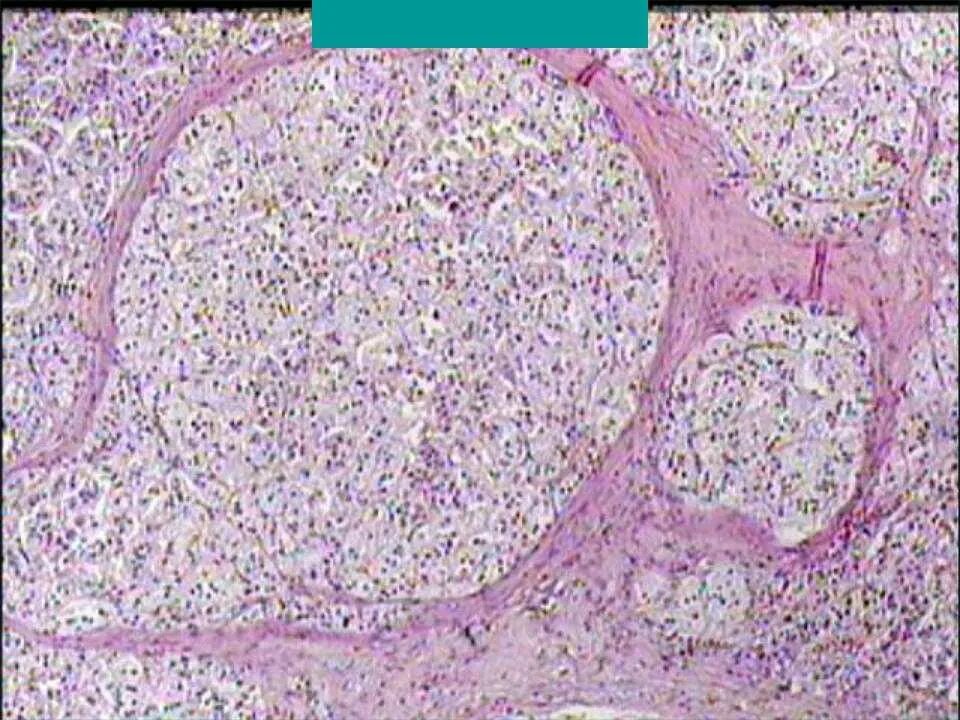

Ли аденома